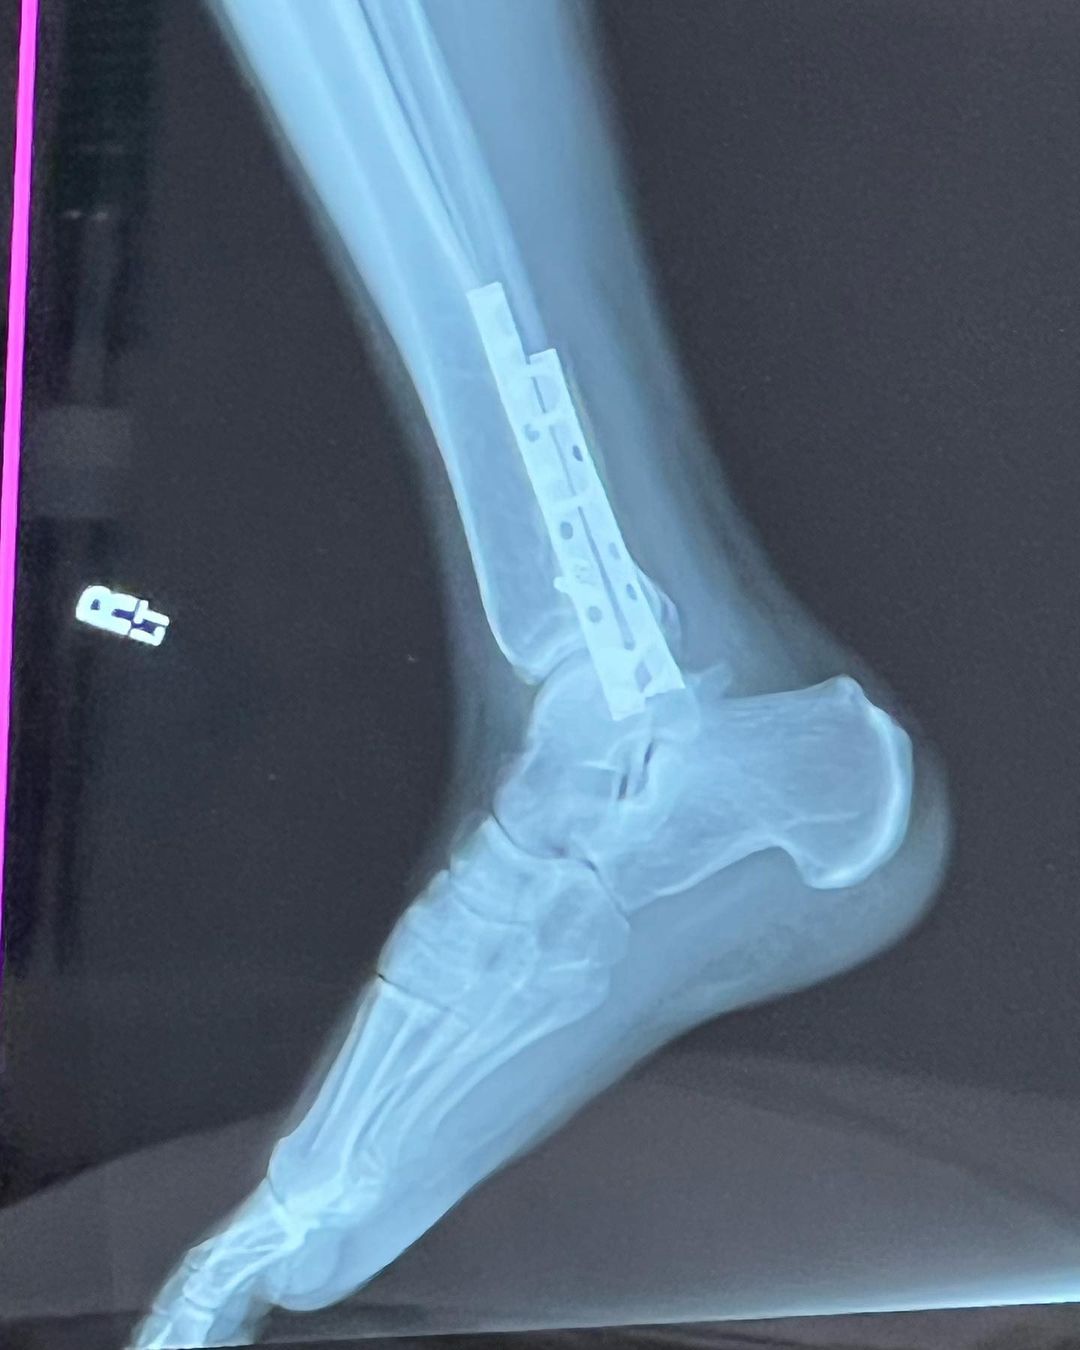

SURGERY UPDATE*

Just got back from my first check up post surgery and everything is looking good.

I was started on some antibiotics just to be safe for possible infection, the doctor said there was a little more red than he would like to see but didn’t think it was infected; it was still a good choice to go on antibiotics though because I was put in a hard cast for two more weeks and we wouldn’t be able to see if it did turn into an infection.